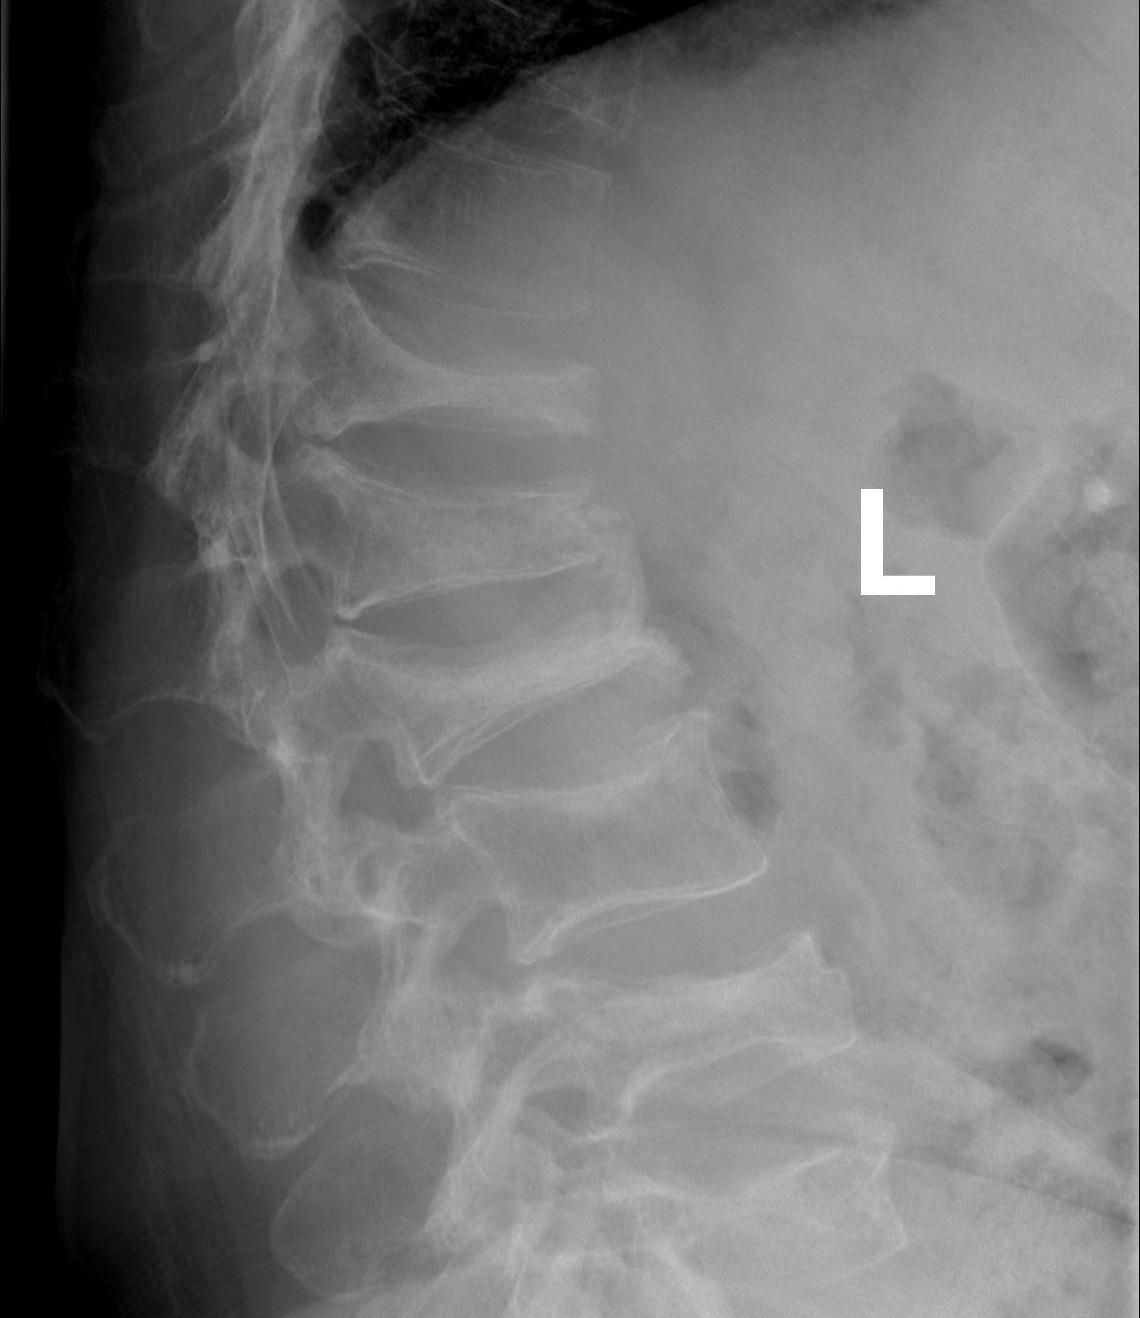

X-ray

1. Punched out lytic lesions

- axial and appendical skeleton

- widely disseminated

- soap bubble appearance

- no sclerotic reaction

2. Diffuse osteopenia

- in 15% to 25% of patients, no discrete lysis occurs

- diffuse osteopenia and osteoporosis are the only skeletal manifestations

3. Vertebrae Plana

4. Pathological Fracture

5. Pepper pot skull

Skeletal survey

Xray

- skull / spine / humerus / femurs / pelvis / chest & ribs

- low sensitivity

- only detect lesions with > 30% cortical destruction